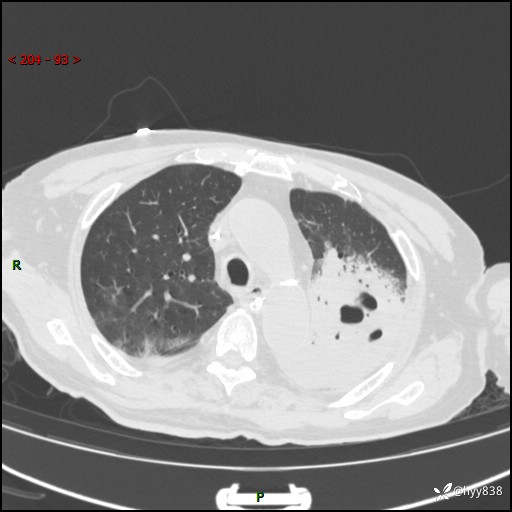

胸部CT平扫(2024.7.24)